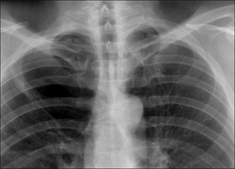

Figure 28.1 Chronic dyspnoea. Extensive alveolar shadowing. Wide differential diagnosis. Apply Golden Rule 1—clinical details are crucial. Known renal failure with fluid retention. CXR conclusion—alveolar pulmonary oedema.